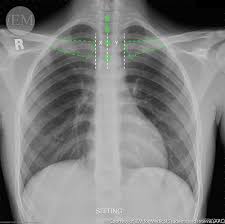

How To Read Chest X Rays International Emergency Medicine Education Project